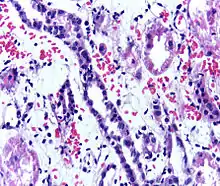

Presence of lymphocytes within the tubular epithelium, attesting to acute cellular rejection of a renal graft. Biopsy sample.

Acute rejection is another possible complication of kidney transplantation; it is graded according to the Banff Classification which incorporates various serologic, molecular and histologic markers to determine the severity of the rejection. Acute rejection can be classified as T-cell mediated, antibody mediated or both (mixed rejection). Common causes of acute rejection include inadequate immunosuppression treatment or non-compliance with the immunosuppressive regiment.[73] Clinical acute rejection (seen in approximately 10-15% of kidney transplants within the first year of transplantation) presents as kidney rejection with associated kidney dysfunction.[73] Subclinical rejection (seen in approximately 5-15% of kidney transplants within the first year of transplantation) presents as rejection incidentally seen on biopsy but with normal kidney function.[73] Acute rejection with onset 3 months or later after transplantation is associated with a worse prognosis.[73] Acute rejection with onset less than 1 year after transplantation is usually T cell mediated, whereas onset greater than 1 year after transplantation is associated with a mixed T cell and antibody mediated inflammation.[73]